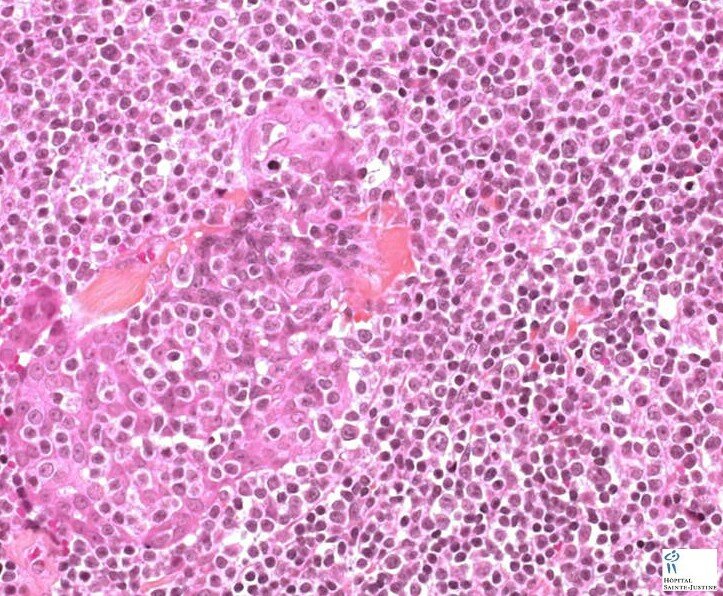

Atypical salivary lymphoid hyperplasia